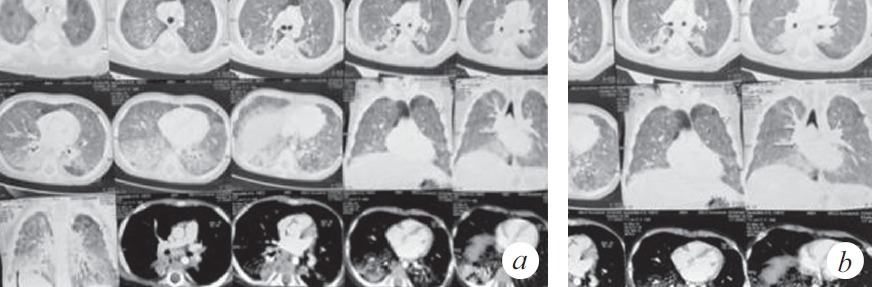

Через 2 нед. госпитализации в ОРИТ у ребенка наросли клинические и параклинические проявления госпитальной пневмонии (лихорадка, повышение С-реактивного белка до 39,7 мг/л), высев грибов рода Candida, Staphylococcus aureus — из верхних дыхательных путей; Еnterococcus faecalis, Еnterococcus fecuim, Klebsiella pneumoniae — из мочи, кала. На контрольной КТ: отрицательная динамика в виде увеличения консолидации в периферических отделах легких (рис. 2), клиническая картина не изменилась. На фоне антибактериальной терапии широкого спектра действия дыхательная недостаточность не прогрессировала, явления инфекционного токсикоза были купированы, кашель отсутствовал. Максимальная оценка по шкале SOFA (Sequential Organ Failure Assessment) 3 балла.

Рис. 2. Компьютерная томограмма органов грудной клетки (через 5 нед. от дебюта заболевания) (a). Признаки диффузного интерстициального повреждения легких. Отмечена отрицательная динамика в виде увеличения консолидации в периферических отделах легких (b)

Fig. 2. CT of the chest organs (5 weeks after the onset of the disease) (a). Signs of diffuse interstitial lung disease. Negative dynamics in the form of increased consolidation in the peripheral parts of the lungs (b)